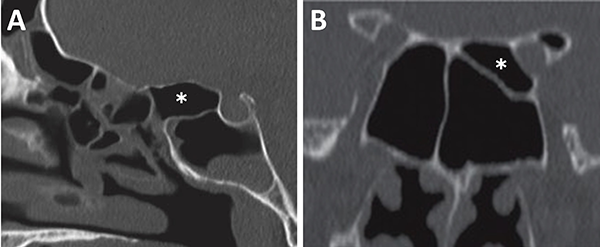

El grado neumatización del seno esfenoidal se puede clasificar en selar, pre selar y conchal (fig. 12).1,29,30,58 En el tipo conchal, el área bajo la silla turca es de hueso sólido sin neumatización. En el tipo preselar, el área neumatizada no penetra más allá del plano perpendicular de la pared selar. En el tipo selar, presente en el 86% de los individuos, la región neumatizada se extiende al cuerpo del esfenoides bajo la silla turca, pudiendo extenderse hacia posterior. Esta característica del seno es importante ya que ante la presencia de un tipo conchal es recomendable la utilización de neuronavegación.23,58

Figura 12: Neumatización del seno esfenoidal en TC cortes sagitales. A) Tipo selar; B) Tipo preselar; C) Tipo conchal.